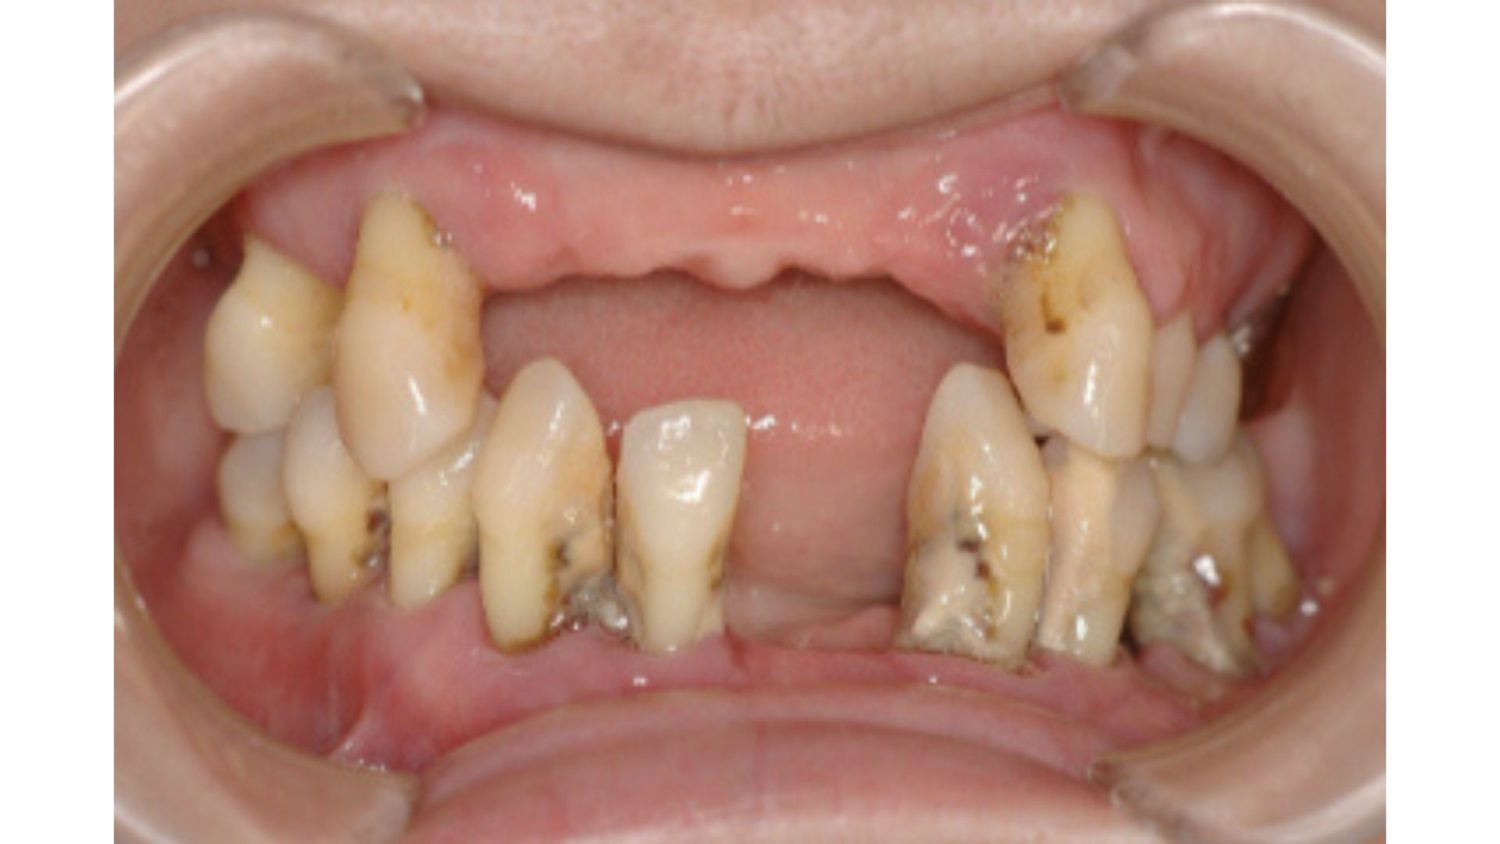

| 主訴 | 全顎治療希望、全顎的に歯が動く、奥の歯がなくて噛めない。できるだけ綺麗で噛めるようになりたい。 |

| 治療内容 | 全顎的に歯周病、前歯部の被蓋が深く、重度歯列不正が認められるため、 歯周外科を含む歯周治療、矯正治療、インプラント治療、セラミックによる補綴治療後メインテナンスに移行しました。 |